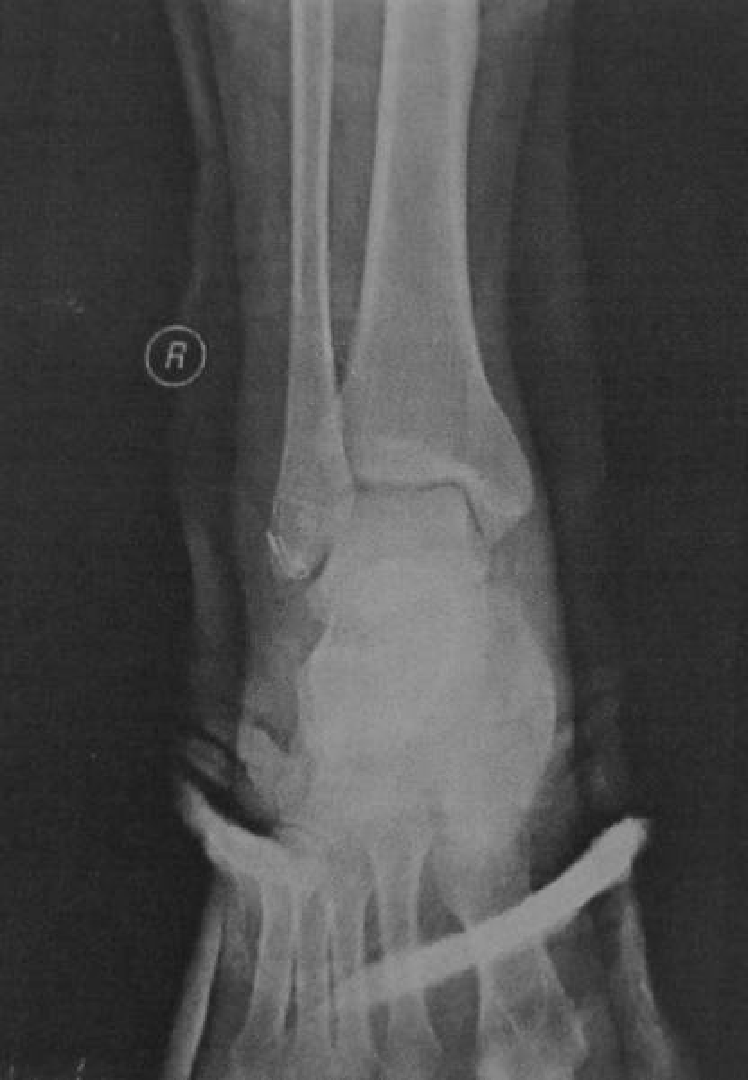

外踝骨折

王岩  男  24岁

软组织撞击

术后复查